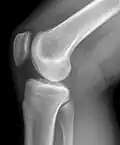

Рентгенограмма коленного сустава в боковой проекции.